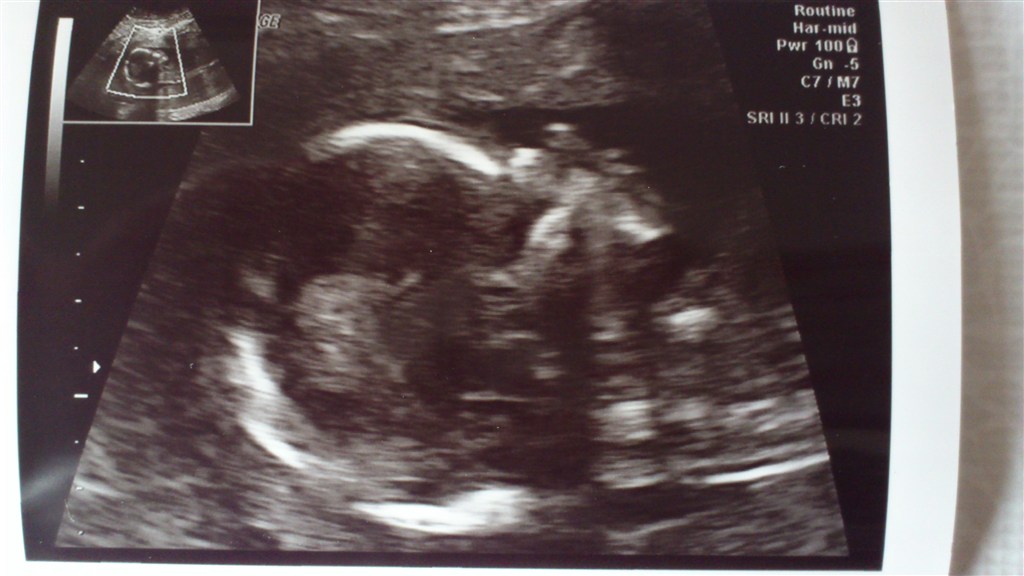

I får lige et par billeder af ham!

Vedhæftede fotos (klik for at se i fuld størrelse)